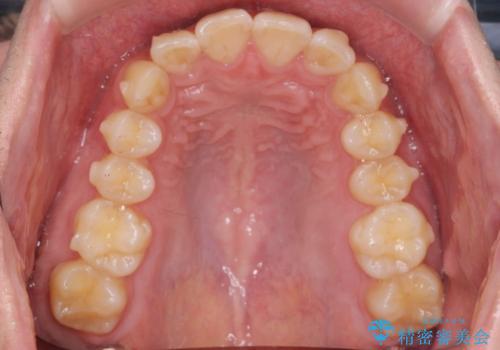

前歯のがたつきをなおしたい マウスピース矯正

- 気になる前歯のがたつきをきれいにしたい。と矯正治療を希望され来院されました。

大きな歯列の乱れはないため、倒れ込んでいる奥歯の傾きの改善、前歯のがたつきを改善する治療を計画します。

見た目が良くなっただけではなく、歯ブラシがしやすくなった!と治療後の歯並びに喜んでいただくことができました。